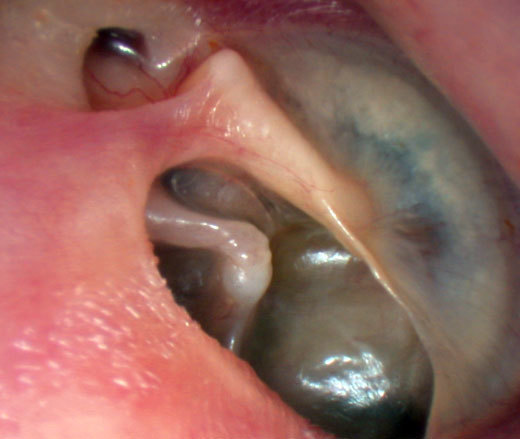

Vous faites un examen du tympan droit. Vous trouverez ci-dessous plusieurs exemples d'otoscopies. Figure 6

Figure 7

Figure 8

Figure 9

Figure 10

Question 8 - Dans le cas d’une fracture du rocher à droite, quelle(s) est (sont), parmi les otoscopies présentées ci-dessus, celle(s) qui est (sont) compatible(s) avec ce diagnostic à 24 heures du traumatisme ?

Tympan normal : la fracture peut ne pas concerner l’oreille moyenne et ne pas entraîner de saignement

Poche de rétraction avec atélectasie postérieure : il s’agit dans ce cas d’une pathologie chronique du tympan, sans rapport avec la fracture du rocher

Otite moyenne aiguë : ce n’est pas le tableau (absence de fièvre), d’autant que le délai est trop bref pour avoir une complication infectieuse

Hémotympan : visualisation d’un hématome dans l’oreille moyenne. C’est l’image typique dans le contexte de fracture du rocher

Myringite bulleuse : c’est ici une complication infectieuse avec la constitution d’une bulle intra-tympanique

Dans un contexte de fracture du rocher, soit le tympan peut être normal, soit le plus souvent il y a un saignement dans l’oreille moyenne et on constate un hémotympan. Cliniquement, l’hémotympan se comporte exactement comme une otite séromuqueuse (présence de liquide dans l’oreille moyenne), cf. les questions suivantes.